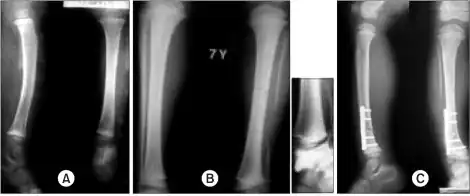

a)Radiographs show a large segmental fibular defect by chronic osteomyelitis b,c) four years later, serial radiographs show a valgus deformity of ankle due to upward migration of distal fibula